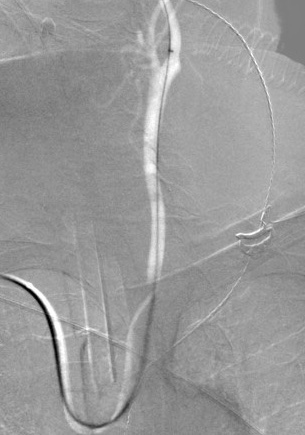

We are proud in Turku University Hospital Finland to be the first in Europe to treat intracranial aneurysms with the redesign Pipeline Vantage flow diverter together with RIST radial access system. Already two patients treated with this excellent combination.